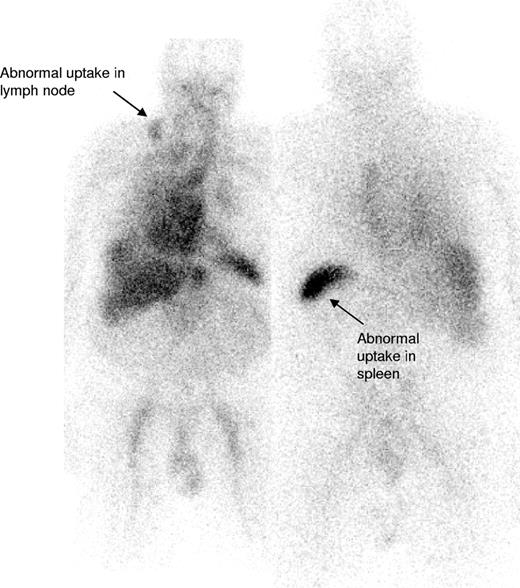

IgM paraproteinemias account for 17% to 20% of patients with MGUS,5,20 and although Waldenström macroglobulinemia (WM) and other lymphomas have been described in association with systemic and localized AL amyloidosis,7,10,21-30 the largest reported series of IgM-associated amyloidosis is 50 patients from the Mayo Clinic in whom treatment outcomes have not been clearly reported.7 The current series of 103 patients accounted for 6% of patients with confirmed AL amyloidosis seen at the NAC between 1988 to 2006, similar to the 5% frequency at the Mayo Clinic.4 In our series, 54% of patients had 2 or more organs involved by amyloid, most frequently the kidneys (53%) followed by the heart (35%), similar to the large previous Mayo series of patients with AL associated with non-IgM monoclonal proteins.4 Lymph node involvement is uncommon in AL amyloidosis associated with non-IgM paraproteins4 but was evident in 21% of patients in our series (Figure 3). Conversely, peripheral neuropathy was less common at presentation, in just 3%, than in previously reported non-IgM series.4,31 None of our patients had lymphoma related “B” symptoms or hyperviscosity syndrome, likely reflecting the observed low clonal burden of their B-cell disorder.

123I-labeled SAP scan from a patient with IgM-associated AL amyloidosis showing uptake of the radiotracer within the involved right cervical lymph node (arrow) in addition to some splenic uptake. There is a normal blood pool tracer signal from the heart and liver.